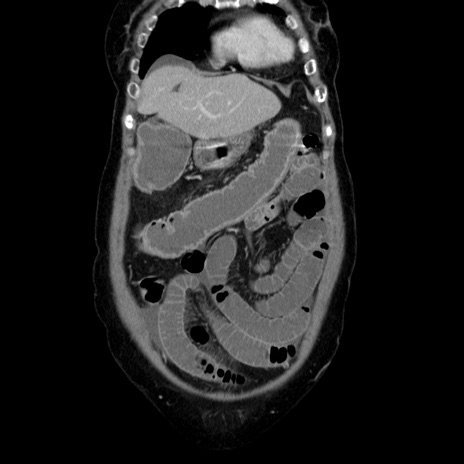

症例5(冠状断像)

横断像

【症例】70歳代女性

【主訴】お腹が張る

【現病歴】1週間くらい前から腹部膨満の自覚あり。昨日夜から増悪したため、本日救急外来受診。

【身体所見】意識清明、BT 36.5℃、BP 165/106mmHg、HR 80bpm、SpO2 98%、腹部:膨満、軟、自発痛・圧痛なし、触診にて不快感あり、腸蠕動音:減弱

【データ】WBC 12600、CRP 1.04